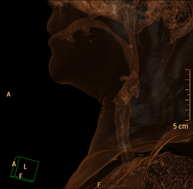

- TC Cuello Prueba radiológica que consiste en obtener imágenes del cuello de alta definición anatómica mediante el empleo de un equipo de TC (Tomografía Computarizada). Indicaciones: estudio de tiroides, control de tumores tratados, estudio de ganglios, infecciones y abscesos. Prueba radiológica que consiste en obtener imágenes del cuello de alta definición anatómica mediante el empleo de un equipo de TC (Tomografía Computarizada). Indicaciones: estudio de tiroides, control de tumores tratados, estudio de ganglios, infecciones y abscesos.

- TC Laringe Prueba radiológica que consiste en obtener imágenes de la laringe de alta definición anatómica mediante el empleo de un equipo de TC (Tomografía Computarizada). Indicaciones: afonía súbita o crónica, dificultad respiratoria. Prueba radiológica que consiste en obtener imágenes de la laringe de alta definición anatómica mediante el empleo de un equipo de TC (Tomografía Computarizada). Indicaciones: afonía súbita o crónica, dificultad respiratoria.

- TC Columna cervical Prueba radiológica que consiste en obtener imágenes de las vertebras cervicales de alta definición anatómica mediante el empleo de un equipo de TC (Tomografía Computarizada). Indicaciones: cervicalgia sin/con irradiación a brazos, traumatismo. Prueba radiológica que consiste en obtener imágenes de las vertebras cervicales de alta definición anatómica mediante el empleo de un equipo de TC (Tomografía Computarizada). Indicaciones: cervicalgia sin/con irradiación a brazos, traumatismo.